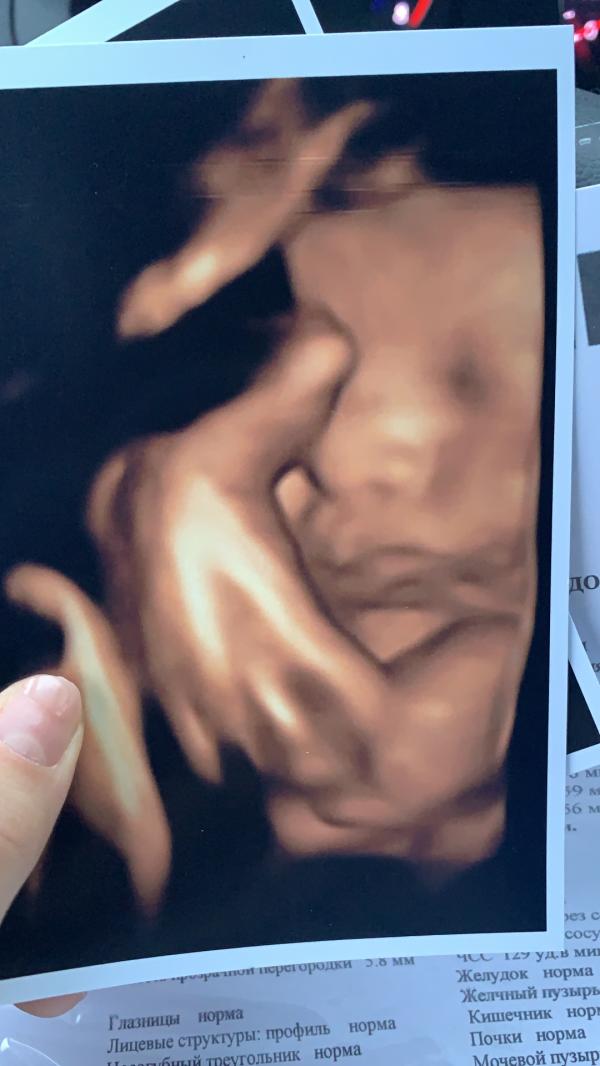

Ура, 36 недель🥰

Начала стирать подушки для кроватки, сумки в роддом собраны❤️

Прибавка веса 11 кг.

Животик начал опускаться, делаю метку на зеркале. Прошли запоры. Периодически мучают тянущие боли внизу живота.

Пдр по 1 скринингу 23 декабря, но почему то думается что рожу до 20 декабря🙈